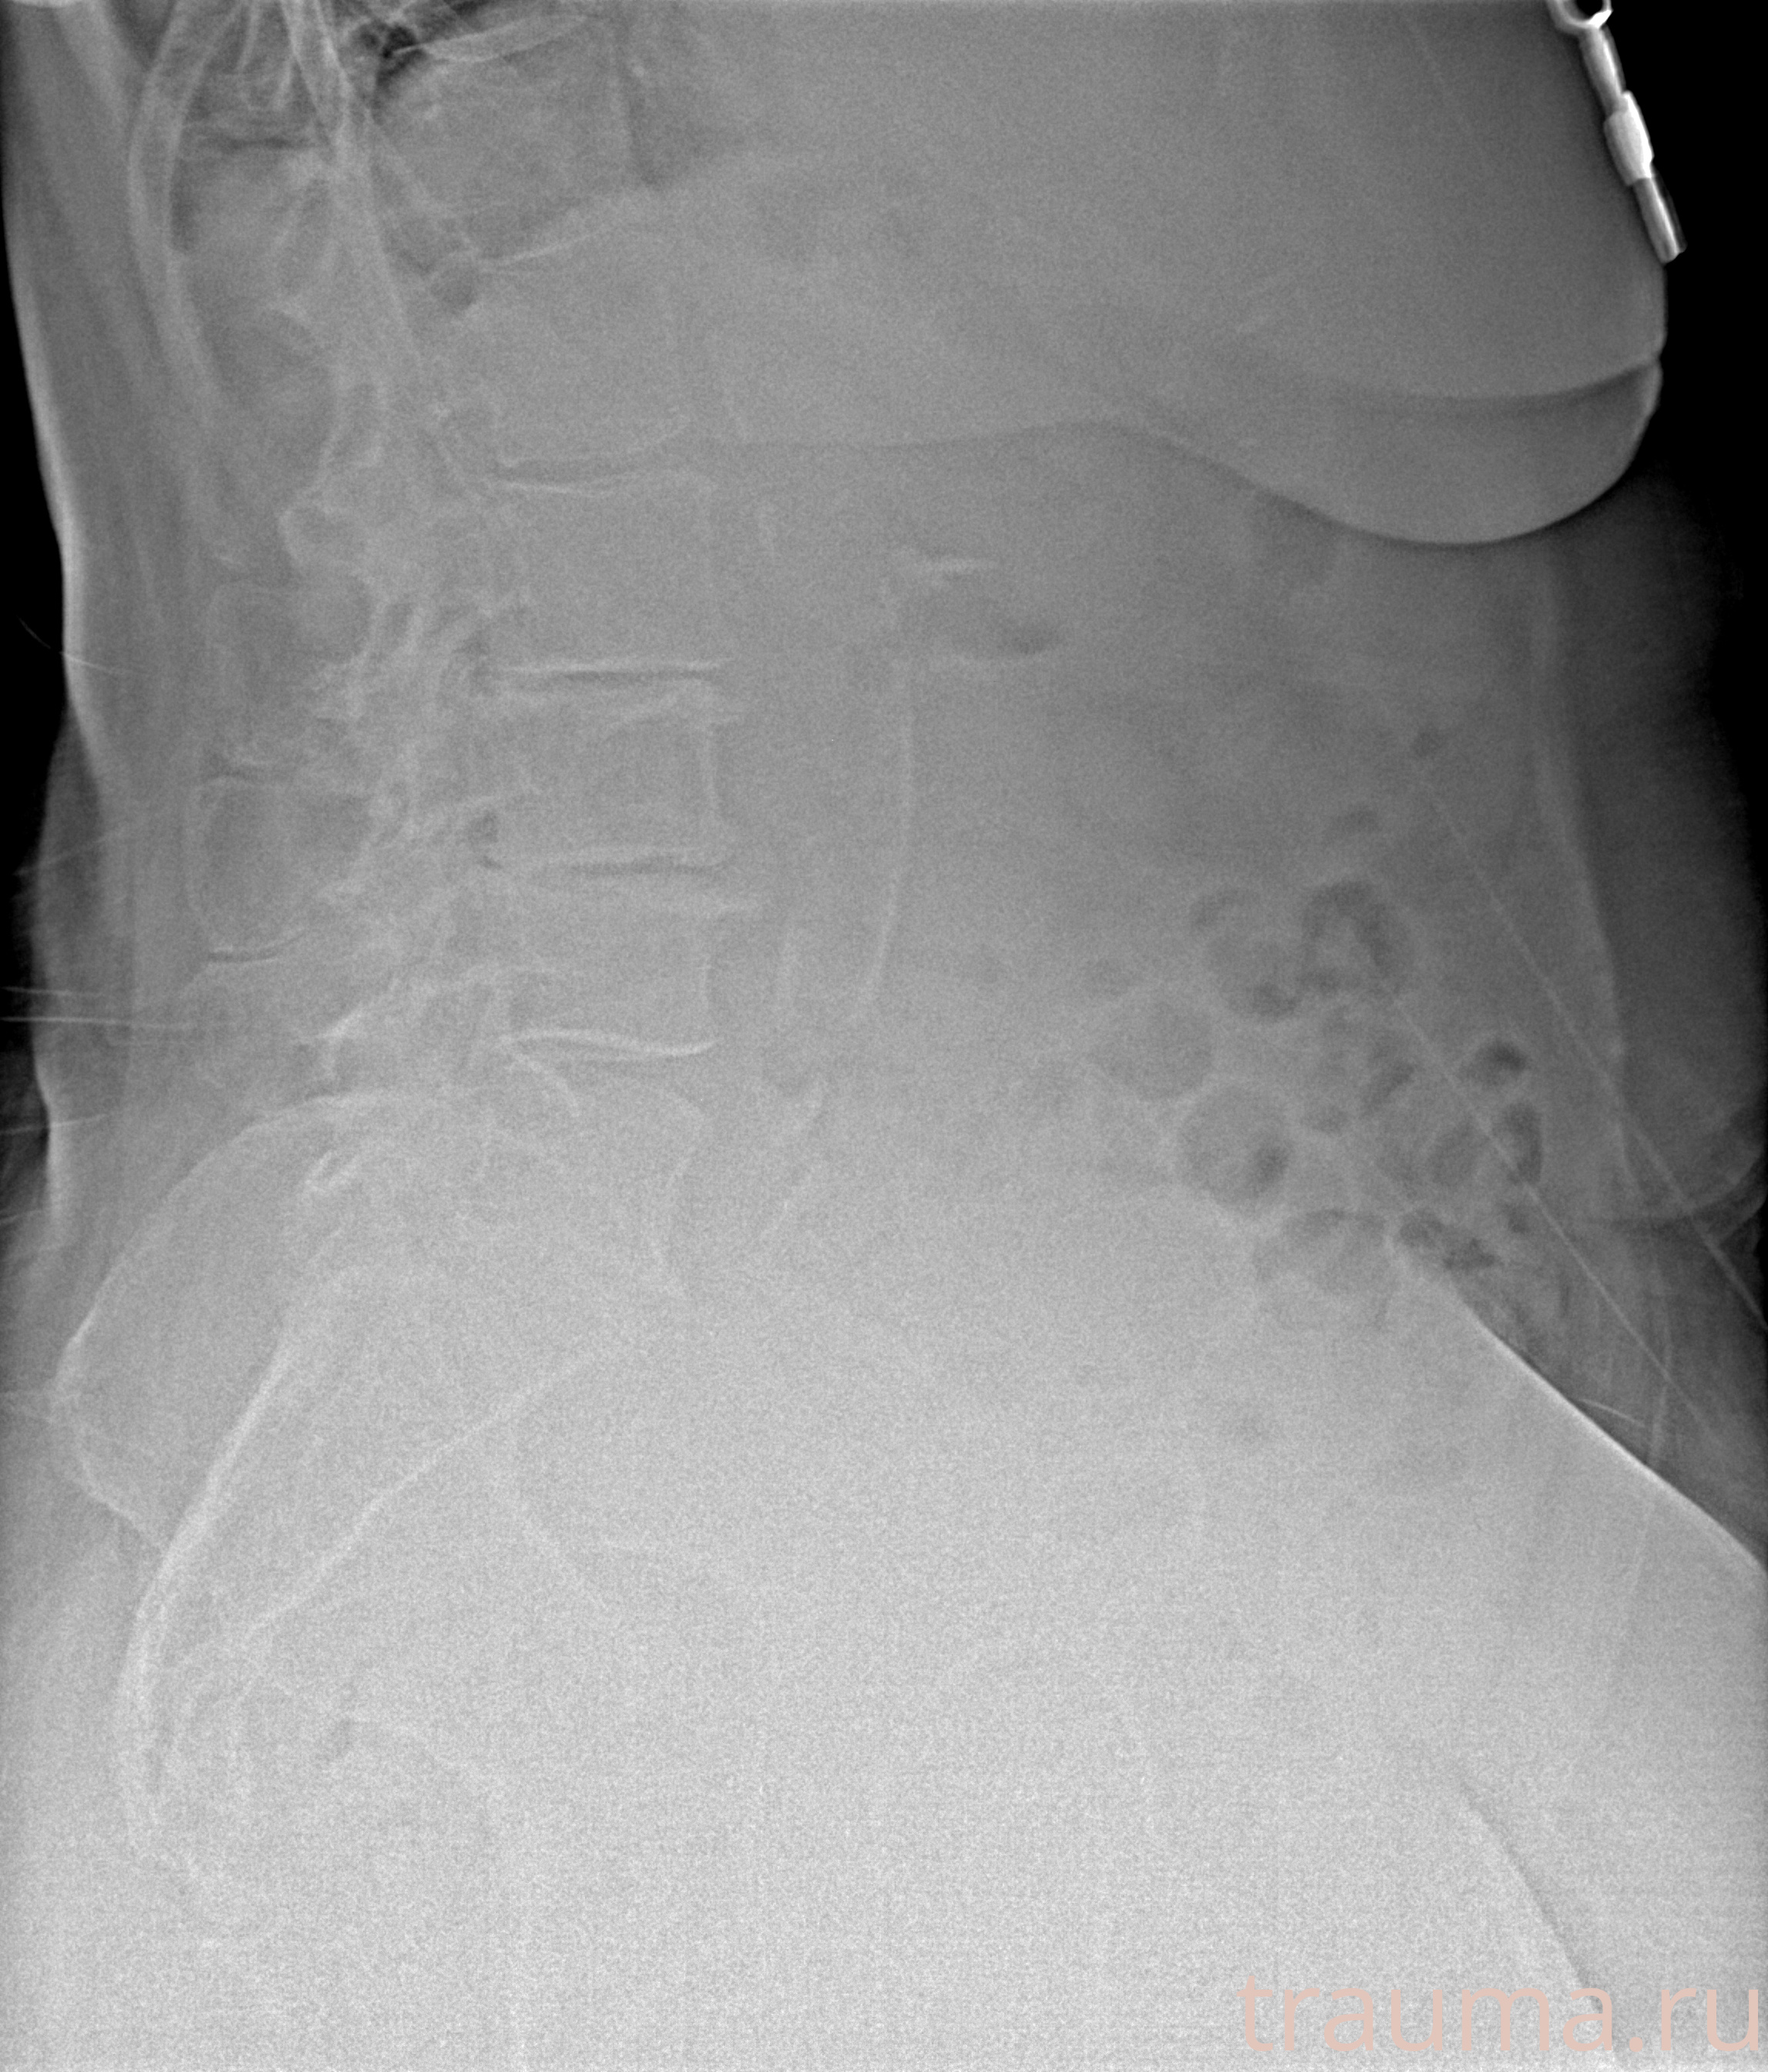

Рентгенограммы

Рентген на дому: по вашему адресу приезжает врач-рентгенолог, травматолог-ортопед с мобильным рентгеновским аппаратом, проводит диагностику травмы или заболевания, делает необходимые рентгенограммы, дает рекомендации по дальнейшему лечению. Получить качественные снимки в домашних условиях возможно благодаря уникальной методике, разработанной МосРентген Центром для института  Склифосовского